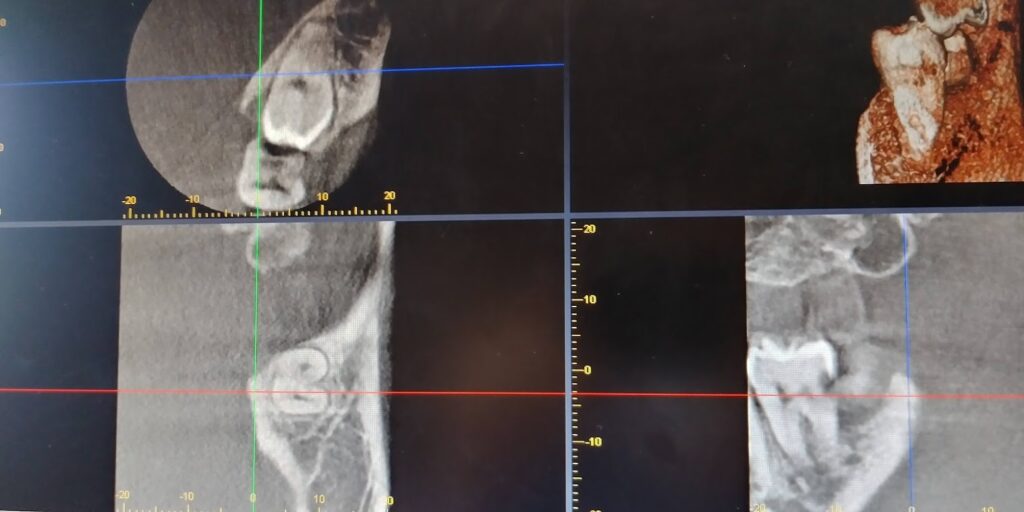

親知らずと虫歯の同時治療 2022年6月25日 最終更新日時 : 2023年11月12日 日航ビル歯科室 左下水平埋伏智歯は手前の左下第2大臼歯を圧迫して、う蝕を誘発しています。 CTでも明らかにう蝕を認めます。そこで抜歯と同時に左下第2大臼歯のう蝕処置を行いました 左下第2大臼歯の歯髄を保護しています。当院では親知らずの手前の歯が虫歯の場合には抜歯の際同時に処置を実施いたします。 親知らずでお悩みの方は、是非当院にご連絡ください!! FacebookXBlueskyCopy